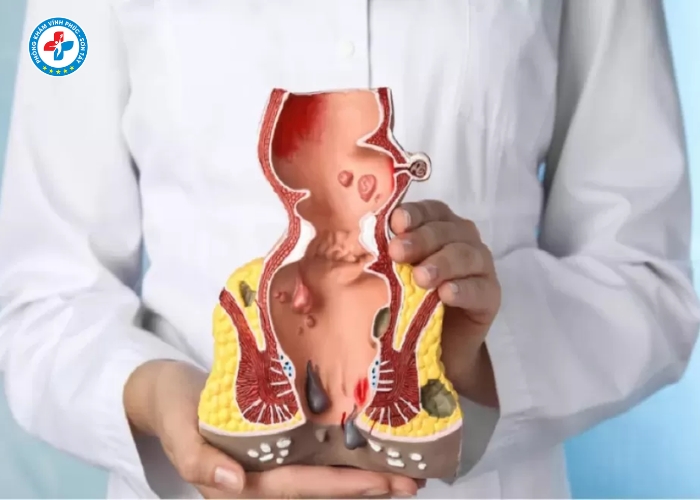

Tiêm trĩ (tiêm xơ búi trĩ) là phương pháp sử dụng thuốc chuyên dụng để tiêm trực tiếp vào búi trĩ nhằm làm xơ hóa mạch máu, giảm kích thước và làm búi trĩ teo dần.

- Chỉ phù hợp với trĩ nội độ nhẹ (độ 1, độ 2)

👉 Trường hợp trĩ nặng (độ 3–4), bác sĩ có thể chỉ định phương pháp khác như cắt trĩ.

Quy trình tiêm trĩ thường được thực hiện theo các bước:

1. Thăm khám ban đầu

- Bác sĩ kiểm tra mức độ trĩ

- Xác định vị trí búi trĩ

3. Tiêm xơ búi trĩ

- Tiêm thuốc vào chân búi trĩ

- Thuốc làm co mạch và xơ hóa búi trĩ